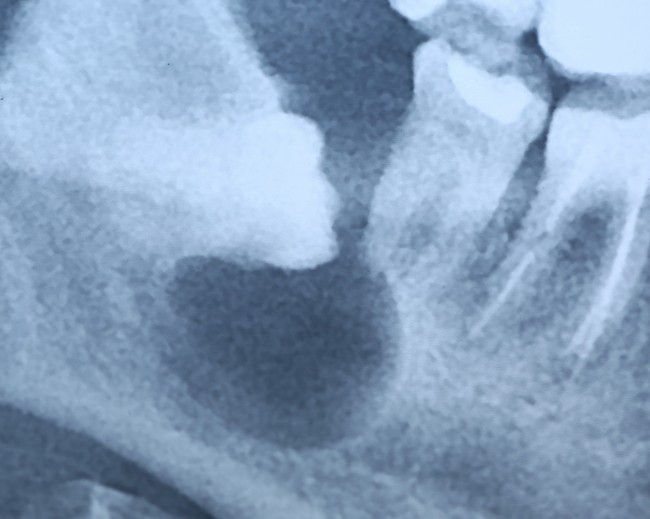

Примерно через три года снимок повторили — уже по другому поводу:

И что мы видим? Под зубом образовалась гигантских размеров фолликулярная киста. То есть, теперь нам нужно не только удалять ретинированный зуб мудрости, но и фолликулярную кисту. А для этого, кстати, придется депульпировать соседний седьмой зуб:

то есть, вместо пустячного и своевременного удаления ретинированной восьмерки, мы получили серьезную проблему, которая, к счастью разрешилась, благодаря случайно сделанному панорамному снимку и вовремя проведенному хирургическому вмешательству.